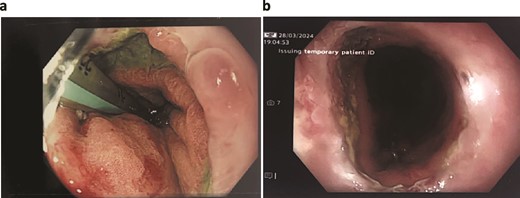

The patient was treated with antibiotics and VACStent insertions, requiring two stent placements (Fig. 1a). By the second stent removal, the anastomotic leak had closed (Fig. 1b). He experienced an episode of acute kidney injury managed with fluids. By postoperative day 24, the leak had resolved, the stent and porta Cath were removed, and the patient was discharged with normal blood results and a follow-up scheduled. The patient continued to manage his overall health with regular follow-ups.

Patient One: (a) Before VACStent insertion, showing the oesophageal defect. (b) After VACStent treatment, demonstrating successful defect closure.